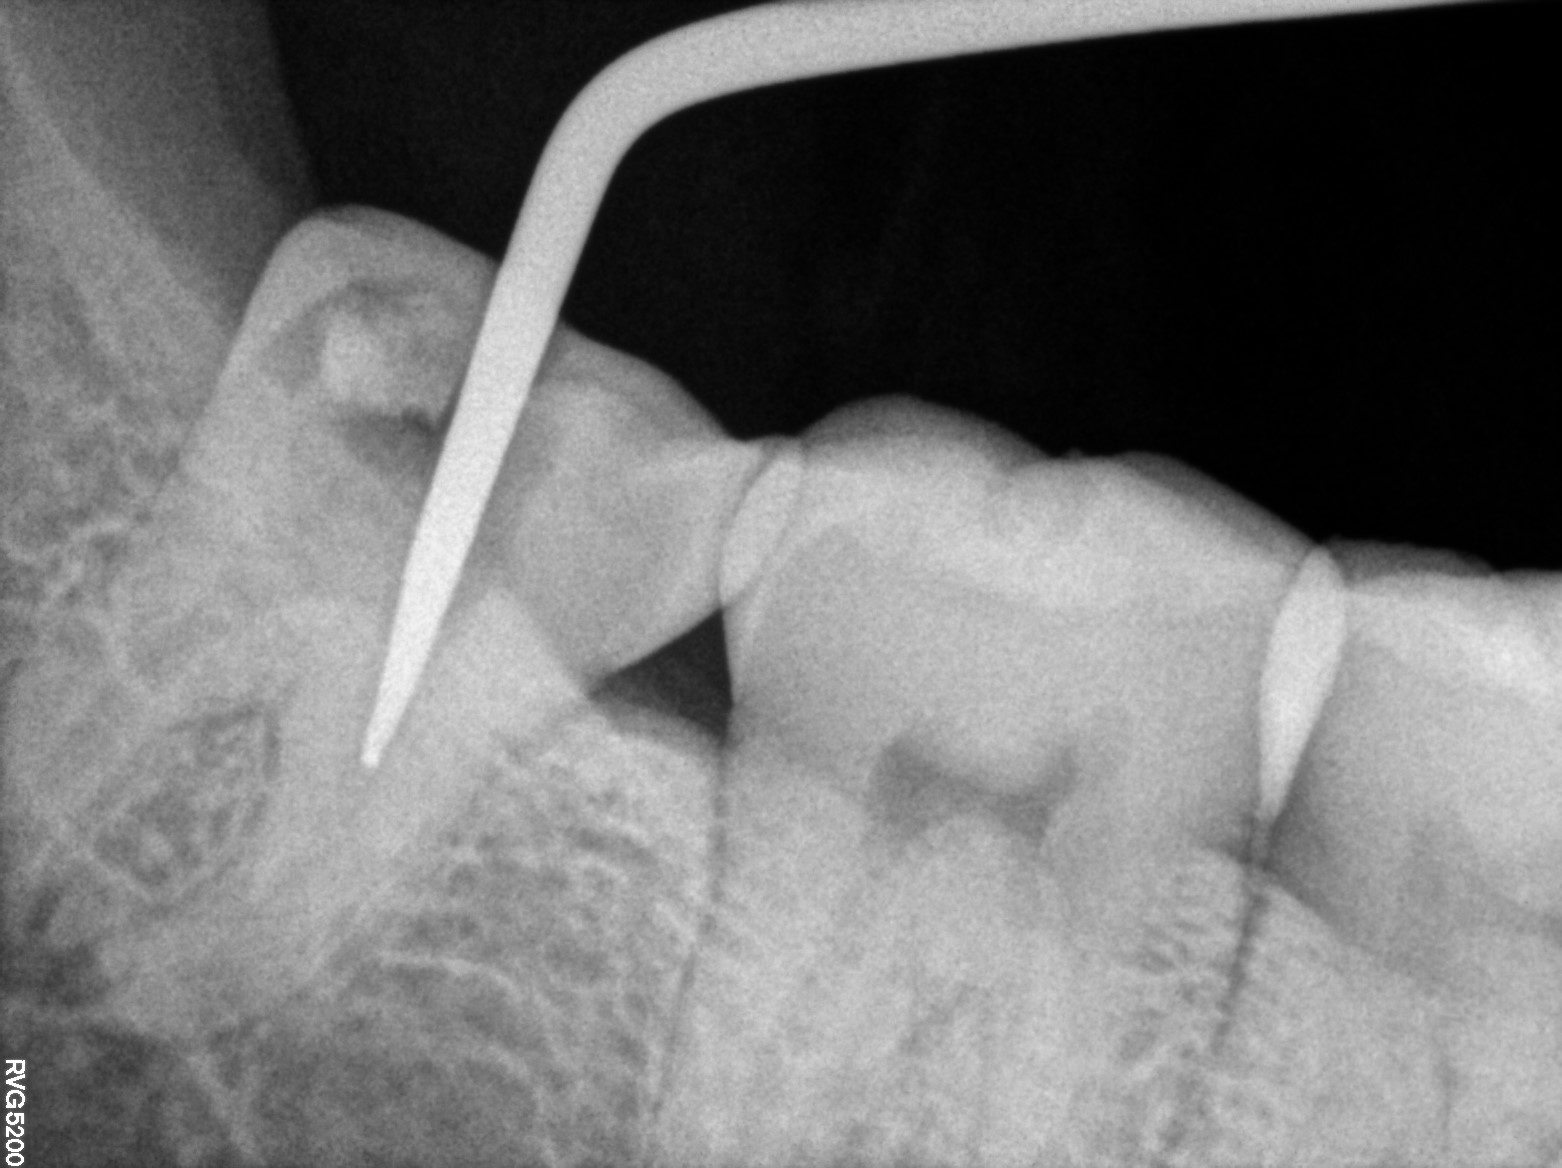

Dental Radiographs FHIR: DocumentReference · LOINC 24641-7

R61.jpg

24641-7